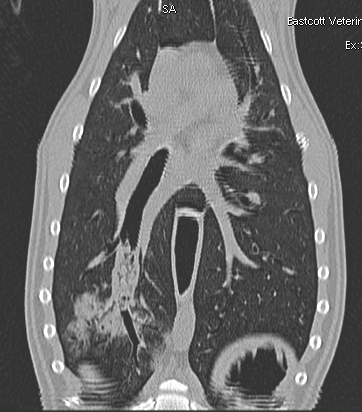

Fig 2

CT image of the bronchial foreign body with the surrounding localized bronchopneumonia